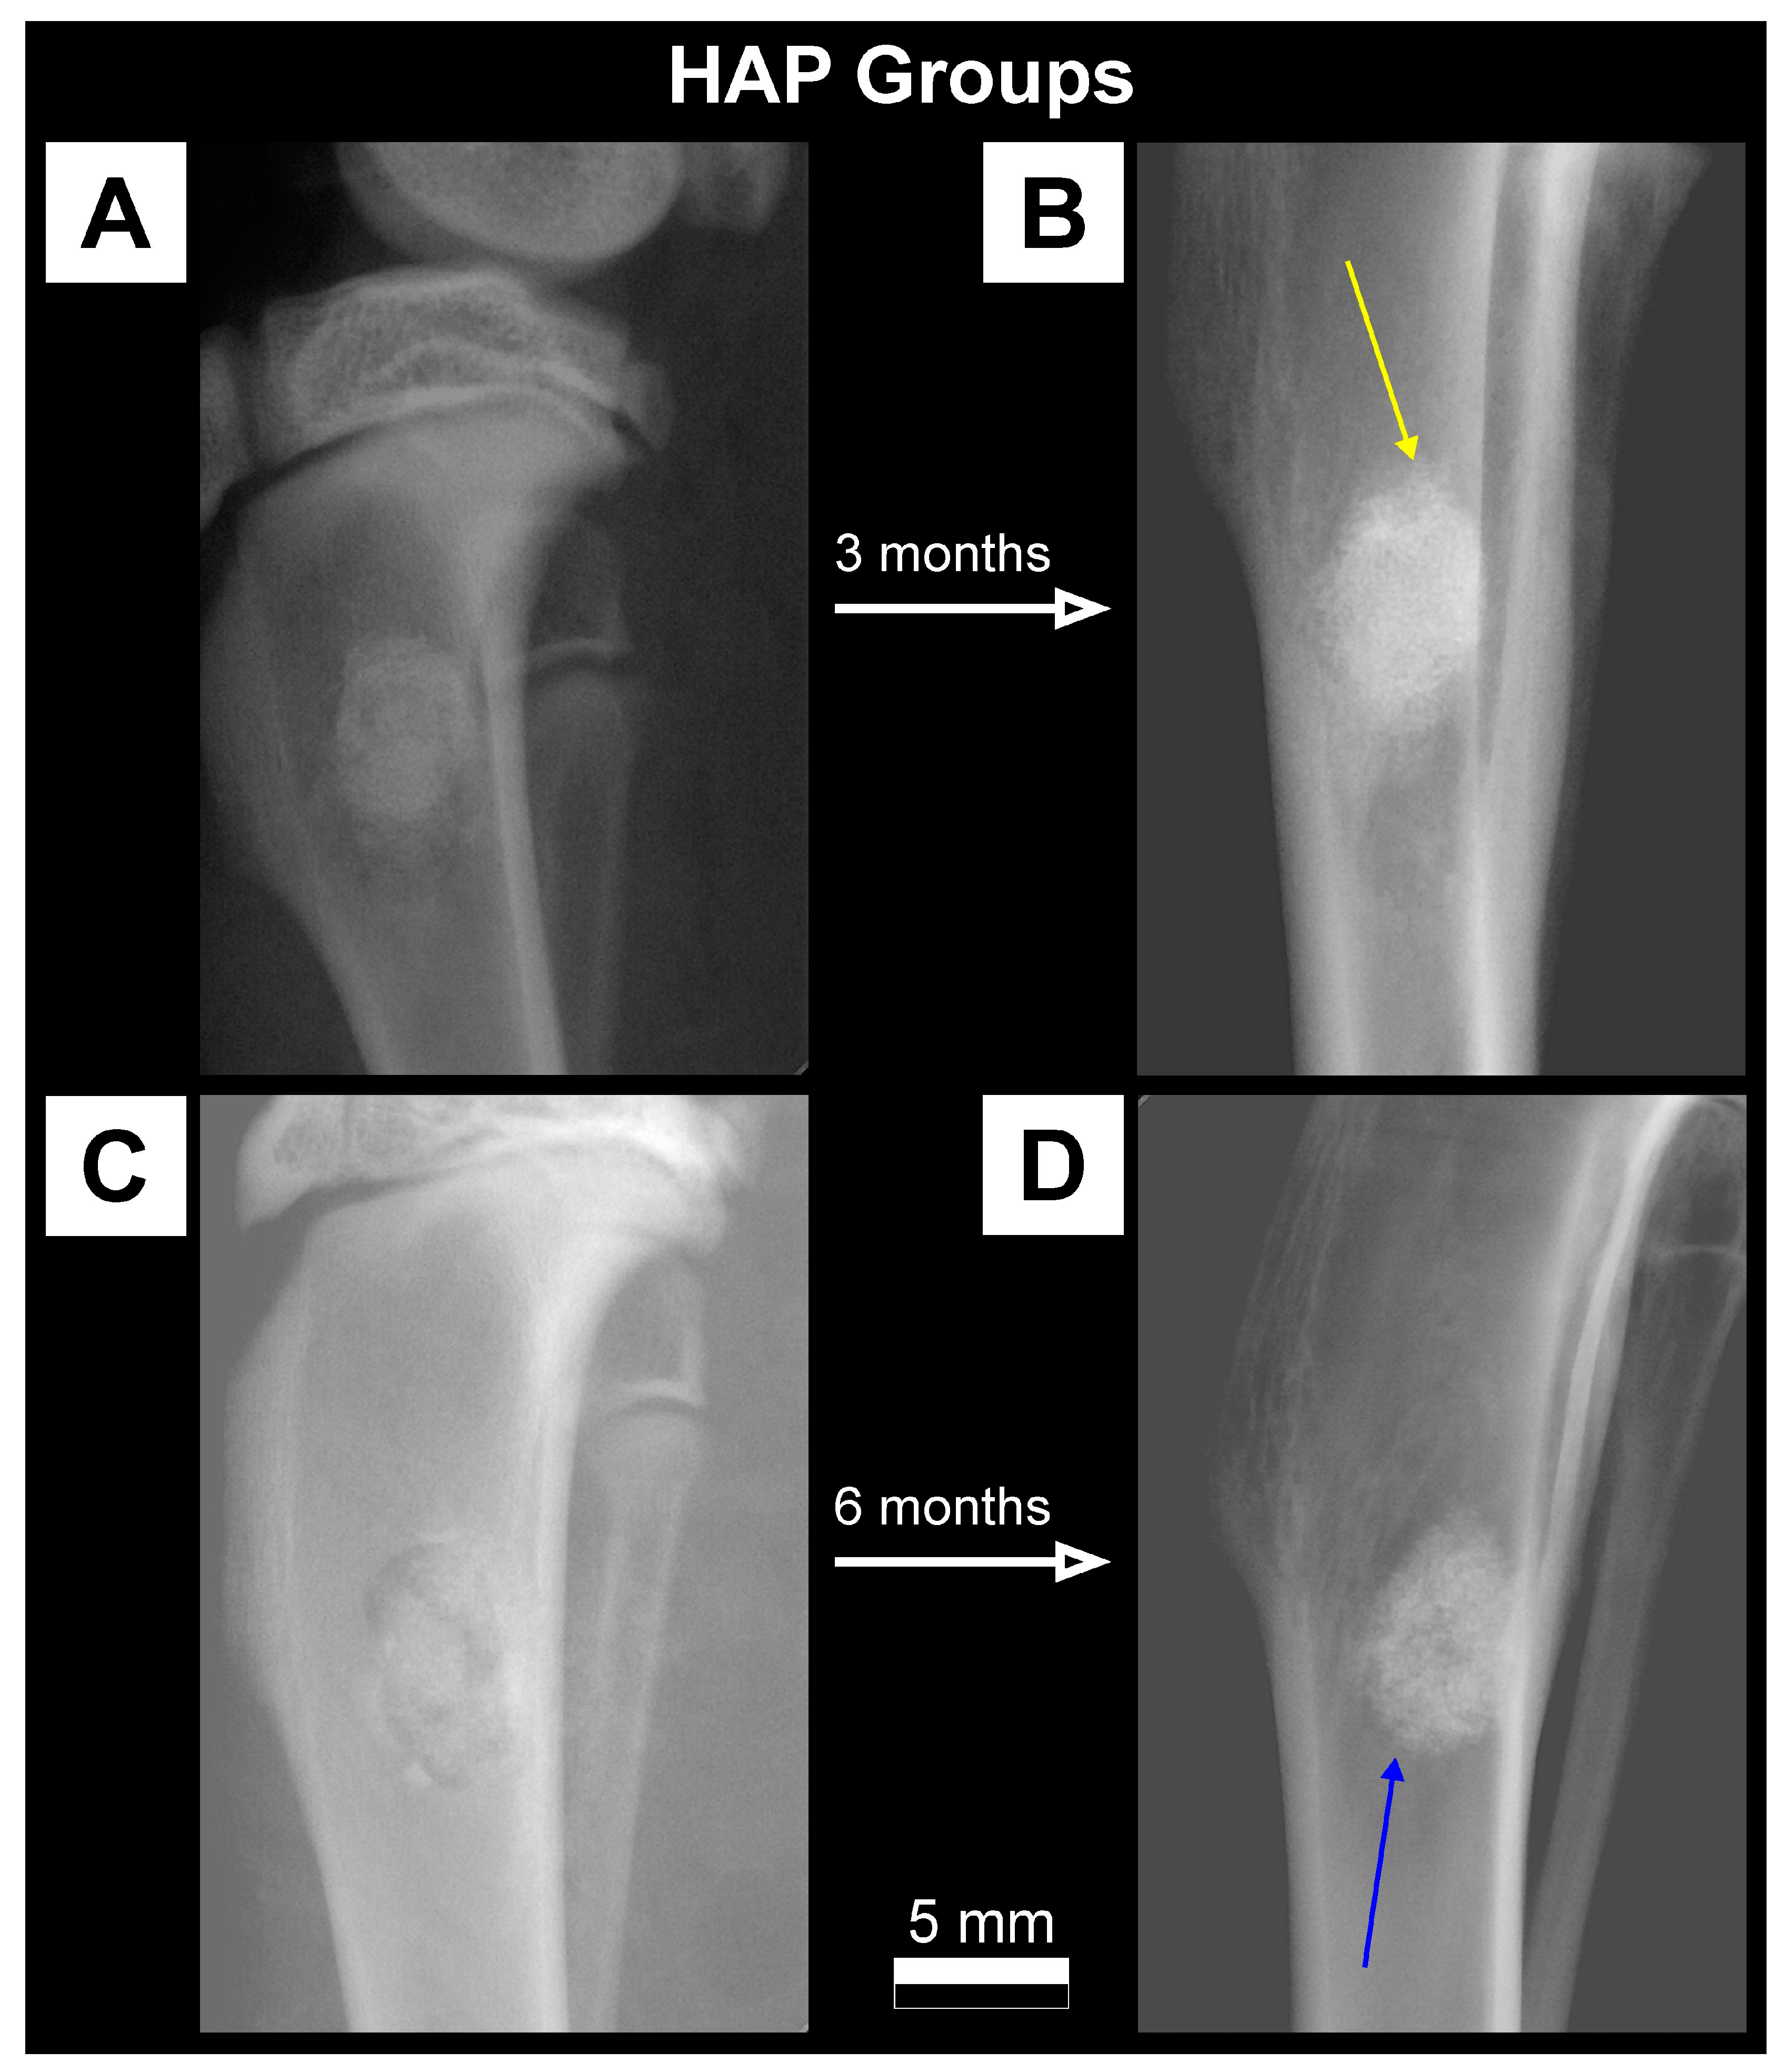

- HAP: Rabbits that have implanted HAP granules (n = 18).

2.3.1. X-ray Imaging—Conventional Radiography

3.1. Qualitative Analysis of Bone Substitute Materials